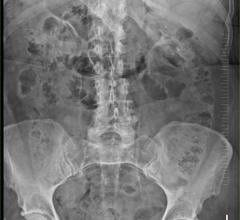

For more than five years, Deer Valley has used the Empower CTA+ Injector System from Bracco Diagnostics. The smart injector technology is designed for the vascular administration of contrast and flushing media in conjunction with computed tomography (CT) scanning of the body. Deer Valley relies on the efficiency of the Empower CTA+ system to enhance patient care while optimizing imaging capabilities, streamlining workflows and improving efficiencies.